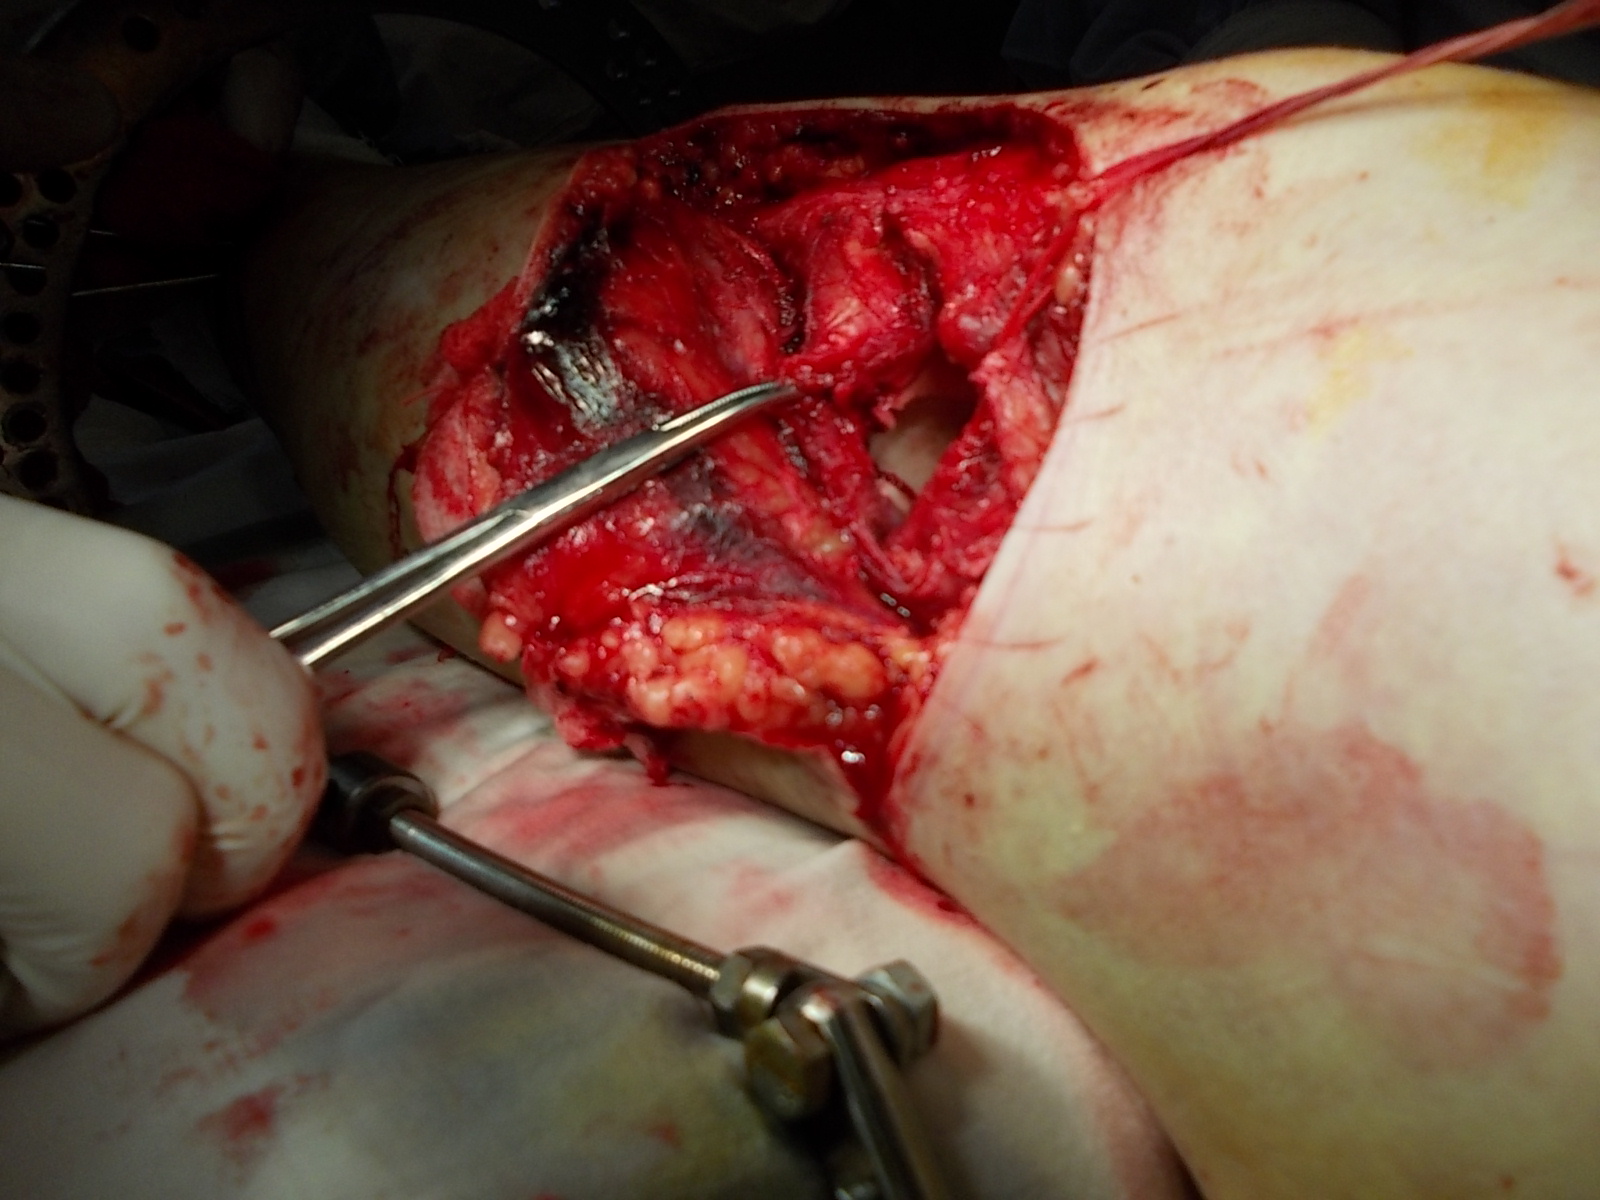

Операция - открытая репозиция, остеосинтез большеберцовой кости опорной пластиной с костной ксенопластикой маетриалом "Остеоматрикс". На контрольных снимках в три и шесть месяцев имеется консолидация перелома, миграции фиксатора нет, имеется остеоинтеграция ксенопластического материала. Функция коленного сустава полная.

Отдаленные результаты через 3 (три) месяца

Отдаленные результаты через 6 (шесть) месяцев

Отдаленные результаты через 14 (четырнадцать) месяцев